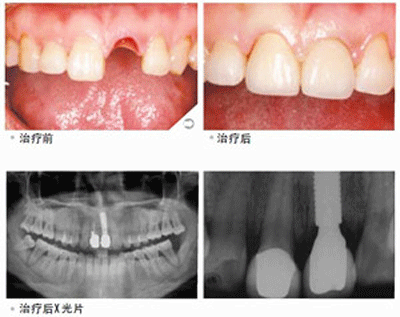

医生介绍,种植牙也叫人工种植牙,是通过医学方式,将与人体骨质兼容性高的纯钛金属经过精密的设计,制造成类似牙根的圆柱体或其他形状,以外科小手术的方式植入缺牙区的牙槽骨内,经过 1~3 个月后,当人工牙根与牙槽骨密合后,再在人工牙根上制作烤瓷牙冠。因不具破坏性,种植牙已被口腔医学界公认为缺牙的首选修复方式。